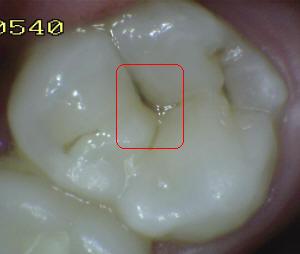

Sistema Internacional para la Detección y Evaluación de Caries (ICDAS)

¿Determine los códigos pertinentes a cada imagen?

Click en el hipervínculo: Para comparar el resultado de su diagnóstico